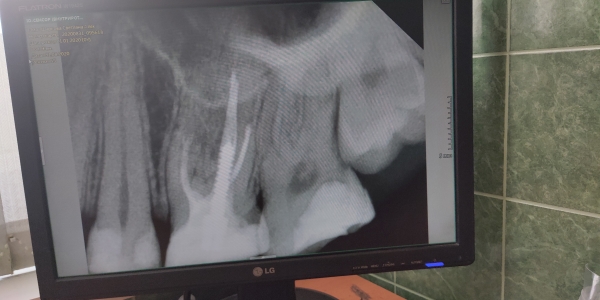

Я сходила на лечение зуба. До посещения врача зуб никак не давал о себе знать, о проблеме выяснилось случайно. Сразу после лечения мне было сказано, что если будет болеть (не уточнили сколько, я предупреждала, что уеду на две недели), нужно прийти на удаление нерва.

После лечения прошла неделя, зуб болит ощутимо. Посетила ближайшие частные стоматологии, там мне сказали подождать еще неделю, так как это может давать о себе знать первое лечение (возможно, туда положили лекарство, и оно действует).

Зависит от интенсивности боли. Если боль самопроизвольная, ночная, то, начался пульпит. Если боль умеренная слабой интенсивности, то, вероятнее всего она пройдет, по мере формирования заместительного дентина.